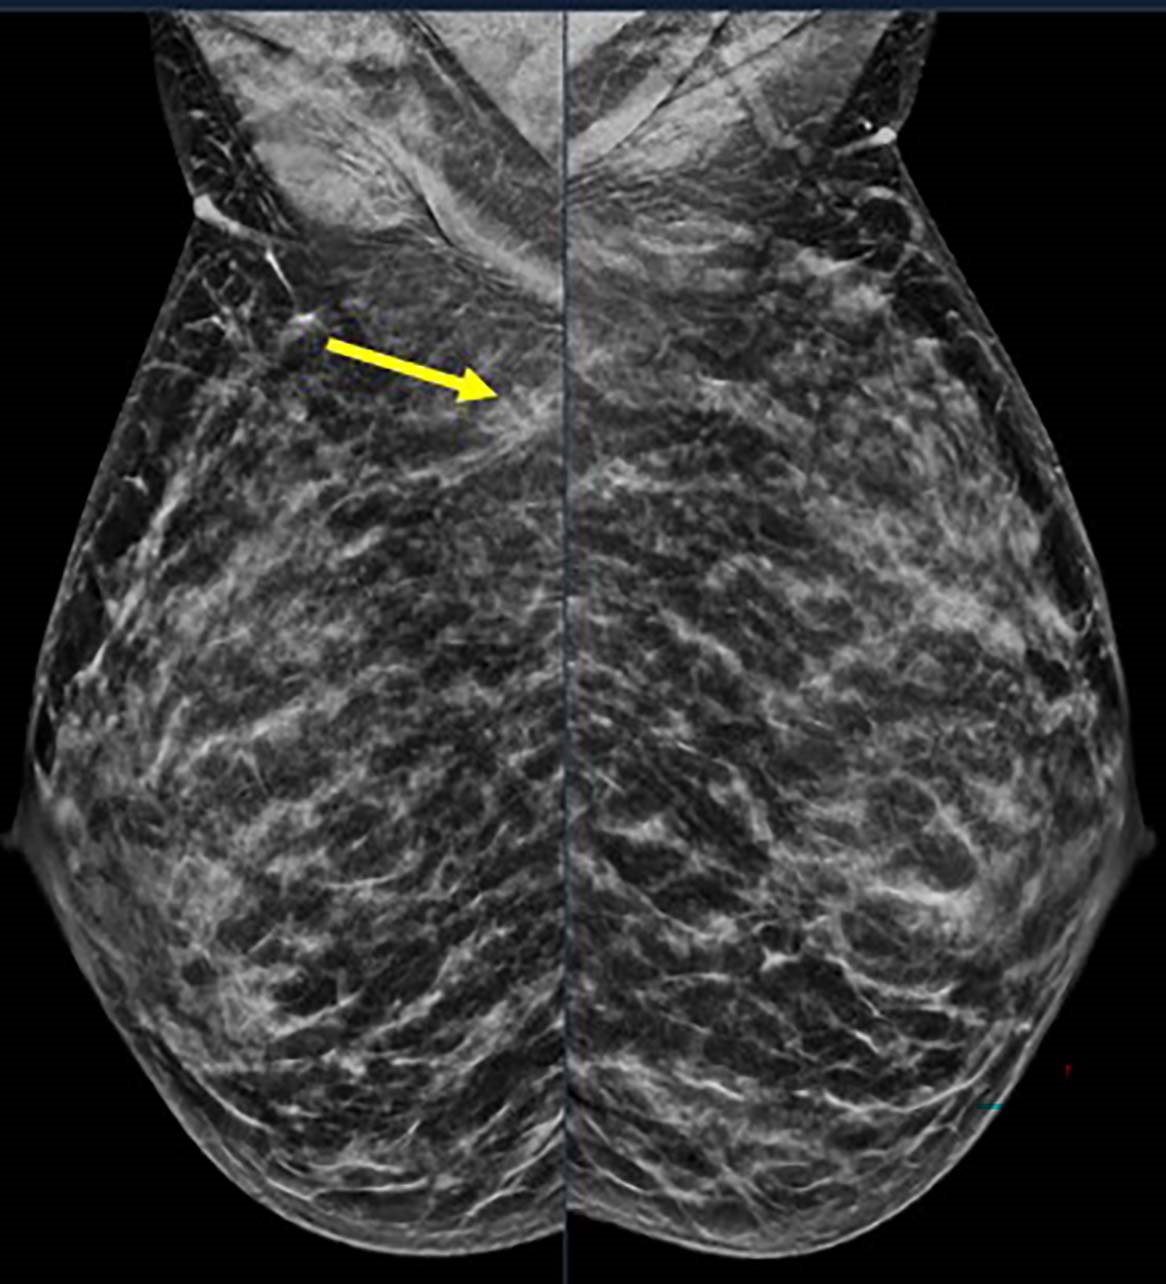

Image credit: Stamatia Destounis, M.D., and RSNA

Dr. Destounis noted that an important factor about the research is that the numbers stayed remarkably stable over the study period, even though fewer young women may have been seen overall, the absolute number of breast cancers in this group did not decrease. “That means this problem is not going away,” she said. “It is here to stay and needs to be addressed on a larger scale. Research such as this supports earlier and tailored screening to allow for earlier detection and better treatment outcomes. This data reinforces that women under 50, especially those under 40, shouldn’t be seen as ‘low risk’ by default and can absolutely benefit from risk assessment being performed as early as possible.”

Dr. Destounis emphasized that the biggest takeaway of the study is that breast cancer in younger women is not rare, and when it does occur, it is often more serious. “We can’t rely only on age alone to decide who should be screened,” she said. “Paying closer attention to personal and family history, and possibly screening earlier for some women, could help detect these cancers sooner.”